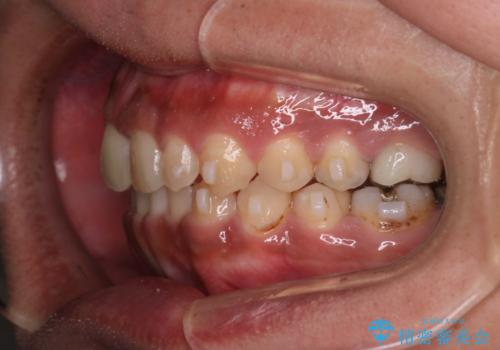

【モニター】インビザライン 前歯の捻れを治したい

- 30代男性

- 矯正装置

- インビザライン

- 上下の前歯のがたつきを主訴に来院されました。インビザラインで治療可能と判断致しましたので、IPR(歯と歯の間を削る処置)と歯列弓拡大をして

がたつきをとる治療計画を立てました。

マウスピースをしっかり使用していただいたことで、主訴である前歯のがたつきも改善され

リファイメントも1回のみで治療を終了することが出来ました。